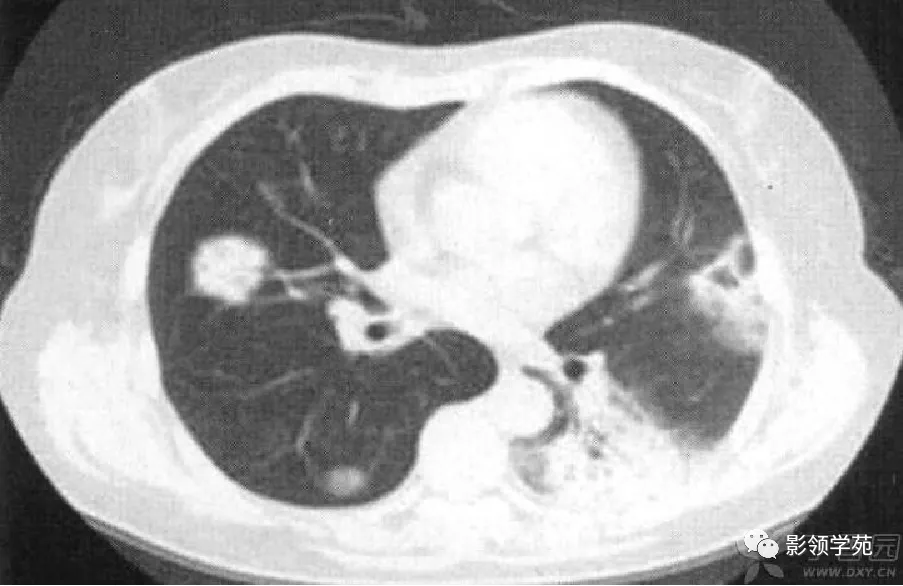

肺感染性肉芽肿

图片尺寸800x519